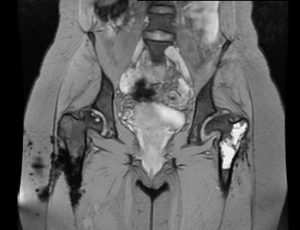

Rezonans magnetyczny (MRI)

Fot.3 Skan z MRI stawów biodrowych

Jest najdokładniejszym badaniem tkanek miękkich, w tym chrząstek stawowych, więzadeł oraz np. obrzęku szpiku po urazach. Nieoceniony w sytuacji podejrzenia i oceny postępowania jałowej martwicy głowy kości udowej, ocenie obrąbka stawu biodrowego w przypadkach jego uszkodzenia. Wykonanie badania nie wymaga skierowania od lekarza, natomiast trzeba pamiętać, że w przypadku wszczepionych sztucznych metali u pacjenta- konieczne jest dostarczenie certyfikatów pozwalających na wykonanie badania. Obecnie większość wszczepionych implantów jest nieferromagnetyczna- oznacza to, że podczas badania nie rozgrzewają się i pozwalają na bezpieczne wykonanie badania. Jeśli pacjent posiada wszczepione implanty i planuje wykonać badanie rezonansu- powinien zgłosić się do miejsca gdzie były one wszczepiane, aby uzyskać wymagany certyfikat.